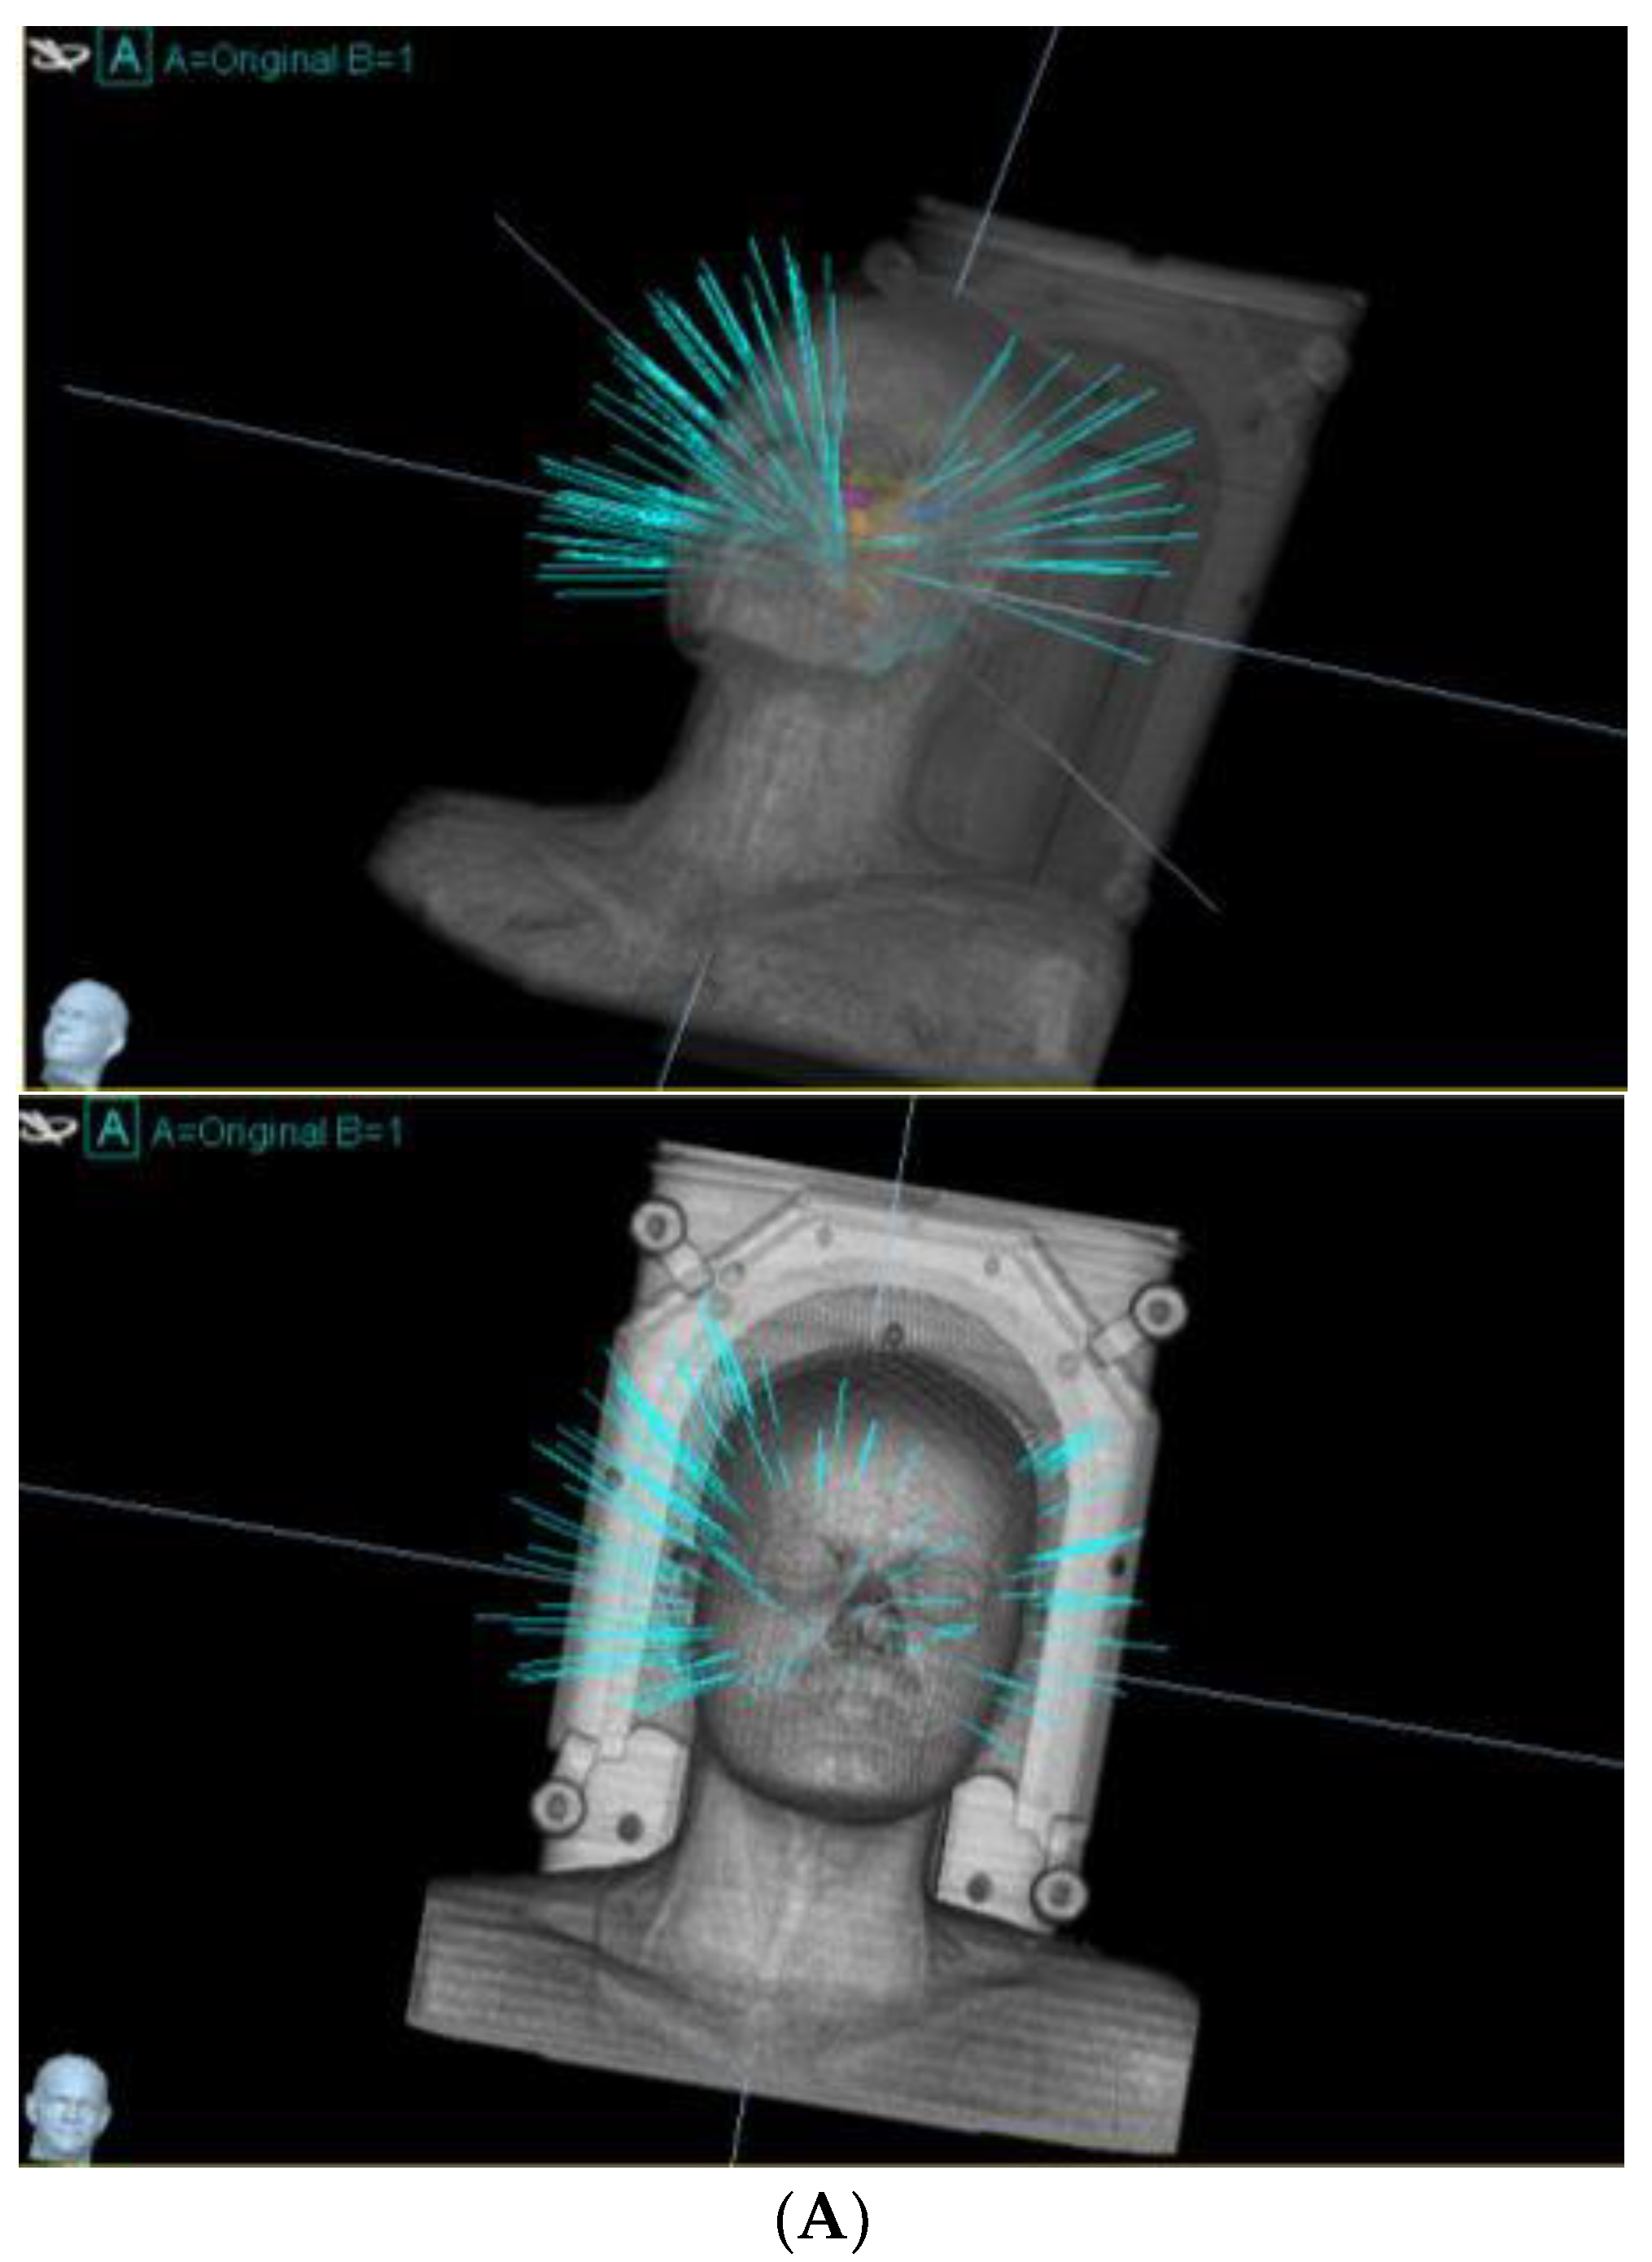

- Giller, C.A.; Berger, B.D.; Pistenmaa, D.A.; Sklar, F.; Weprin, B.; Shapiro, K.; Winick, N.; Mulne, A.F.; Delp, J.L.; Gilio, J.P.; et al. Robotically guided radiosurgery for children. Pediatr. Blood Cancer 2005, 45, 304–310. [Google Scholar] [CrossRef]

- Mohamad, O.; Wardak, Z.; Bowers, D.C.; Le, A.H.; Dan, T.; Abdulrahman, R.; Gargan, L.; Klesse, L.; Weprin, B.; Swift, D.; et al. Margin-Free Fractionated Stereotactic Radiation Therapy for Pediatric Brain Tumors. Pract. Radiat. Oncol. 2020, 10, e485–e494. [Google Scholar] [CrossRef] [PubMed]

| Mohamad et al./2020 [19] | To compare fractionated CyberKnife with IMRT in pediatric brain tumors. | 52 pediatric cases treated with CyberKnife. Dosimetry compared with IMRT. | CyberKnife reduced normal tissue radiation volumes without compromising local control (3-year local tumor control: 92%). | Fractionated CyberKnife reduces irradiated tissue volume; results warrant prospective validation. |